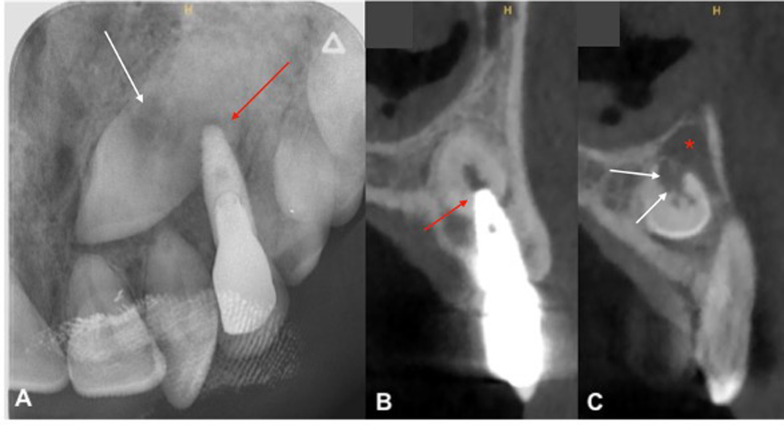

Case presentation: A 42-year-old man presented with persistent swelling and pain in the maxillary region associated with a transcanine implant placed one year ago by his dental practitioner. Imaging assessment showed the implant's apex inserted into the impacted canine which presented a crown and root resorption and was associated to a radiolucency around. In order to preserve implant and reduce morbidity related to a full extraction of the tooth, a coronectomy was performed allowing inflammatory surrounding tissues curettage.